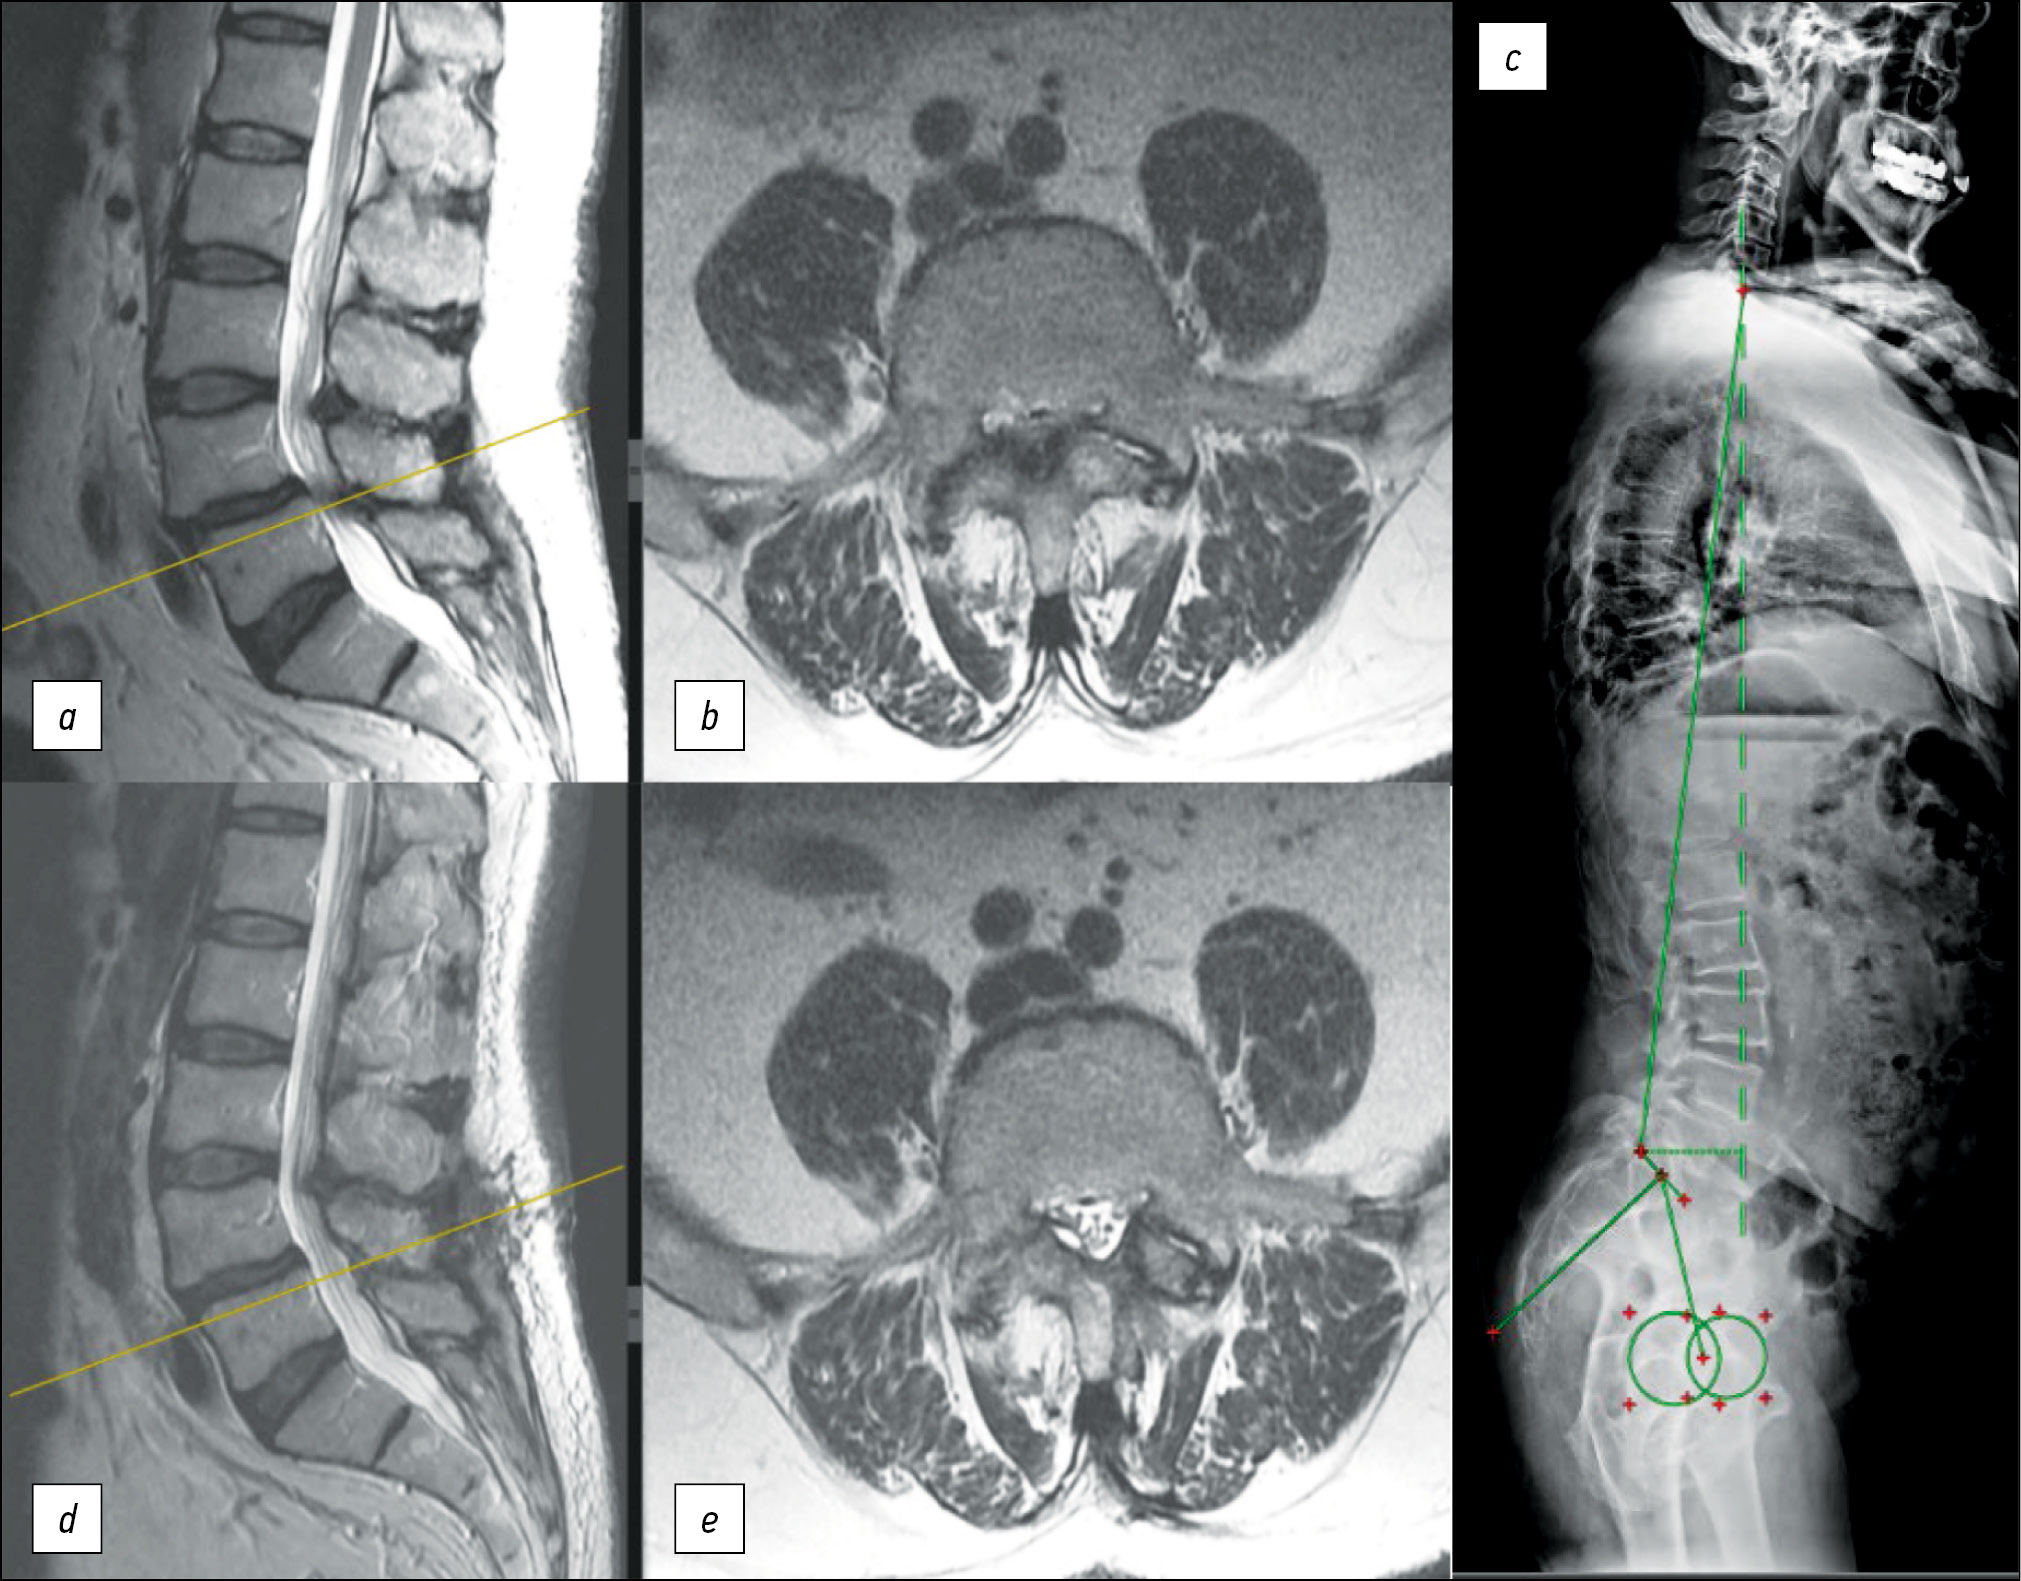

Рис. 1. Пациент Б., 83 года: ВАШ спины — 5 баллов, ВАШ ноги — 8 баллов, ODI=47,5%, DN4 — 2 балла; a, b — МРТ поясничного отдела позвоночника — дегенеративный стеноз на уровне L4-L5 степени D по Schizas, дегенеративный спондилолистез L4 I степени; с — постуральная рентгенография позвоночника — индекс Barrey=1,76, хирургическое лечение — микрохирургическая декомпрессия «over-the-top» на уровне L4-L5; d, e — МРТ поясничного отдела позвоночника через 1 год — рекалибрация позвоночного канала до степени А4 по Schizas, ODI — 4,0%, ВАШ ноги — 0 баллов, ВАШ спины — 3 балла. Достигнут клинический успех — регресс по ODI на 43,50%, рекалибрация позвоночного канала, удовлетворённость оперативным лечением по шкале Ликерта — 5 («гораздо лучше, чем перед операцией»). Достигнут успех лечения.